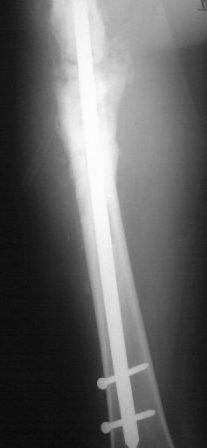

Представляю контрольные послеоперационные рентгенограммы. Во время операции была выделена зона перелома небольшим разрезом, произведена декортикация. Окончательный остеосинтез.

Все участникам обуждения большое спасибо за советы и рекомендации.

На снимках все выглядит хорошо, поздравляю. Декортикацию только делали напрасно, но уж что сделано, то сделано.

Спасибо! Для рассверливания канала предварительно из зоны перелома выполнили перфорацию сверлом диаметром 6 мм, т.к. на протяжении практически 10-12 см в зане перелома склерозированная кость с кистозными полостями. Из зоны перелома были удалены рубцовые плотные ткани. Окончательно формировали каналя с использованием полугибких риммеров. Канал рассверлили до 10 номера, гвоздь № 9 длиной 380 мм. Посев из зоны оперативного вмешательства отрицательный. Для контроля 3 суток назад посеяли отделяемое по дроенажу (геморрагическое). Дренаж удалили на 3-и сутки. насегодняшний день 6 сутки, заживление первичное. По окончании установки гвоздя в канал осуществили компрессию до уровня плотного соприкостновения костных отломков, после чего длокирование гвоздя. Визуально есть участок около 1,5-2 см где гвоздь визуализируется, но вспоминая длительный остемиелит от допонительного использования трансплантатов отказались.